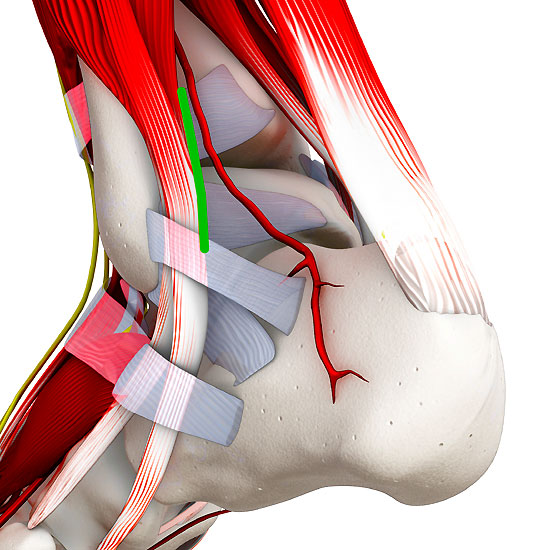

Abbildung 2: K-Draht Spreizer. Dieser erlaubt eine Distraktion des Gelenks über 1,8 mm Kirschnerdrähte. Diese Technik hilft in nahezu allen Fällen eine Innenknöchelosteotomie zu vermeiden.

Abbildung 2

• Sprunggelenk Basisinstrumentarium.

• Spreizer mit Bohrungen für Kirschnerdrähte (Abbildung 2).